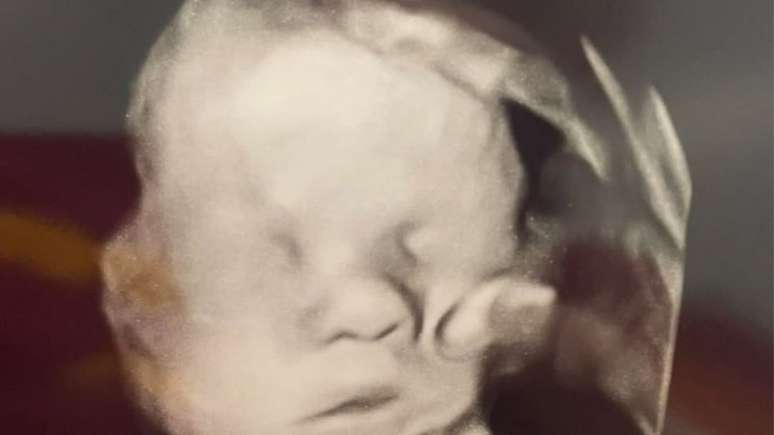

Após oração, mãe, que já havia perdido bebê, vê mão misteriosa no ultrassom

A caçula que foi responsável por notar a mão misteriosa sobre a face de seu irmão no ultrassom; veja mais detalhes sobre esta história

Foto: Reprodução Facebook/Believe in Jesus Christ / Bons Fluidos

Mão misteriosa no ultrassom

A mulher de 33 anos está grávida de um menino há oito meses, e antes do ultrassom, por repetidas vezes, pediu "para que Deus mantivesse sua mão no bebê". Isso porque o pequeno havia sido diagnosticado com uma condição no coração no início da gestação. Mais especificamente, a parede que separa o órgão da artéria aorta estava com problemas, o que estava arriscando a vida do menino.

Sendo assim, depois da oração, ela, o esposo Kyle, e sua filha mais nova, Bailey, entraram para a sala do procedimento. E a caçula que foi responsável por notar a mão gigante sobre a face de seu irmão. "Depois de ter ficado bastante tempo pensando sobre isso, acabei chorando e fiquei repleta de gratidão por tudo o que Deus continua fazendo por mim", a mulher disse, em entrevista ao site 'Daily Mail'.

Muitos internautas duviraram ao ver a publicação no Facebook e alegaram que se tratava da mão do pequeno distorcida. Apesar disso, o casal acredita que uma força maior estava protegendo o filho.